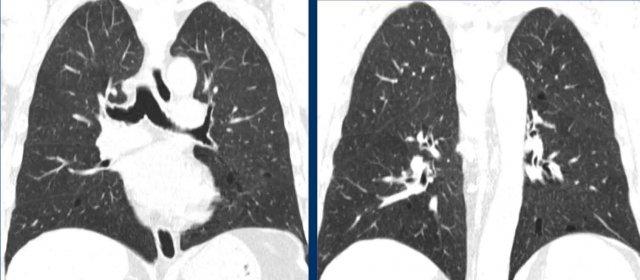

LCH khởi phát dưới dạng các nốt, sau đó tạo hang và chuyển dạng thành các nang với hình dạng bất thường (nang kỳ dị, do sự hợp nhất của hai hoặc nhiều nang với nhau).

Hình ảnh

- Các nang có hình dạng kỳ dị ở một bệnh nhân nam mắc LCH.

- Trường hợp nặng của LCH giai đoạn tiến triển, hình ảnh tương tự khí phế thũng. Ở một bệnh nhân nữ không có tiền sử hút thuốc, đây cũng có thể là trường hợp LAM (bệnh cơ trơn bạch huyết) nặng.

- Nhiều nốt, một số đang tạo hang, với phân bố ưu thế ở vùng phổi trên (khác với di căn), và hoàn toàn không tổn thương các ngách màng phổi.

- Sự kết hợp giữa các nang kỳ dị, các nốt và các nốt đang tạo hang với phân bố ưu thế ở vùng phổi trên.

Đây là hình ảnh của một bệnh nhân nam 66 tuổi, có tiền sử hút thuốc lá và đến khám vì triệu chứng khó thở.

Hãy phân tích hình ảnh.

Đâu là dấu hiệu đặc trưng nhất?

Chẩn đoán có khả năng nhất là gì?

Nhận xét hình ảnh

Ghi nhận nhiều nang.

Một số có hình dạng bất thường và một số có dấu hiệu “cheerio” (hình vòng tròn) do hiện tượng tạo hang bên trong nốt (mũi tên trắng).

Ngoài ra còn ghi nhận một số nốt (mũi tên đen).

Bình luận

Sự kết hợp của các dấu hiệu này trên một bệnh nhân hút thuốc lá là điển hình cho chẩn đoán LCH.

Tiếp tục…

Trên tái tạo mặt phẳng coronal, có thể thấy rõ ràng rằng các nang chủ yếu tập trung ở thùy trên và thùy giữa, trong khi vùng đáy phổi được bảo tồn.

Đặc biệt khi LCH còn ở giai đoạn nốt, sự phân bố này có thể là dấu hiệu hữu ích trong việc phân biệt với di căn phổi, vốn có xu hướng ưu thế ở thùy dưới.

Đây là một trường hợp tương tự.

Lưu ý rằng các nang chủ yếu tập trung ở thùy trên và thùy giữa.

Các ngách màng phổi được bảo tồn.

Các nang đã gây ra tràn khí màng phổi.

Đây là hình ảnh của hai bệnh nhân khác nhau.

Mặc dù thoạt nhìn hai hình ảnh này trông có vẻ tương tự nhau, có thể nhận thấy rằng ở bên trái là các nang thực sự có thành trong một bệnh nhân LCH giai đoạn tiến triển, trong khi ở bên phải một số tổn thương có vẻ có thành nhưng phần lớn thì không.

Đây là hình ảnh khí phế thũng trung tiểu thùy.